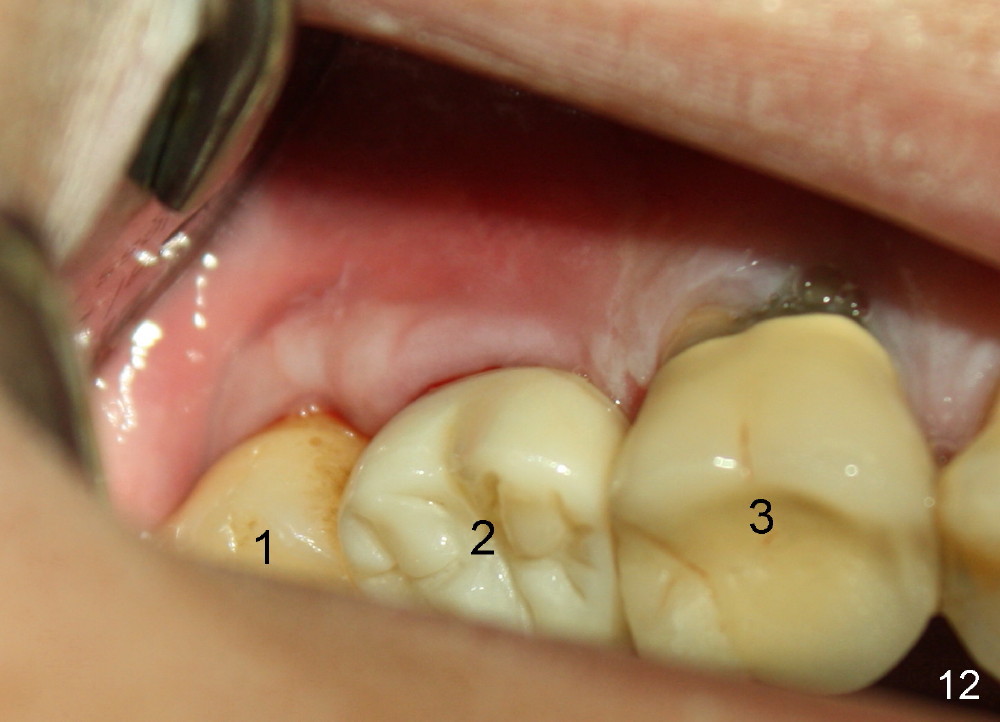

Six months post cementation, the patient returns for follow-up (Fig.11-14) with chief complaint of food impaction between the upper right last 2 teeth. It is difficult to remove. The distal 2nd thread appears not to be covered by the bone, whereas the mesial one is (compare Fig.11 arrowheads). The buccal gingiva is apparently within normal limit (Fig.12) except the distal (Fig.13 >). The distolingual gingiva recession is much more severe (Fig.14). There are deep pockets with tenderness in the abnormal sites. The tooth #1 has #2 mobility with tenderness. The patient agrees to have it extracted and restored with an implant, since the tooth #32 is functional. Bone graft will be placed in the lingual aspect of the implant at the site of #2.